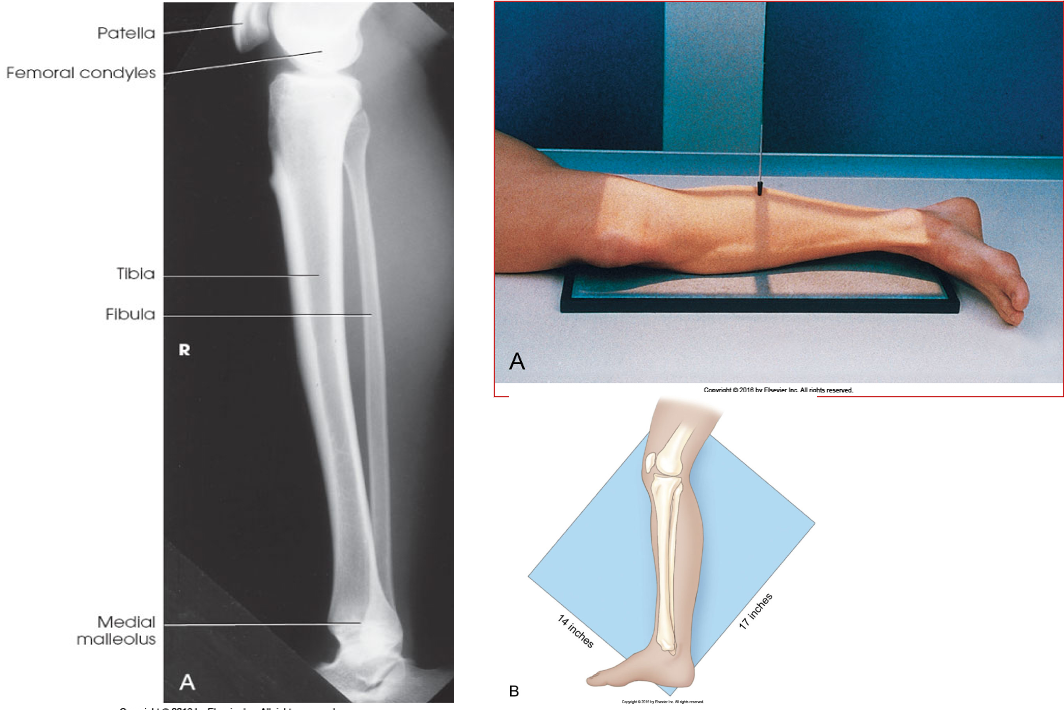

AP Tib/Fib

• IR 14x17 portrait (or diagonally), 48” SID

• Pt supine with leg extended fully. Align pelvis, knee & leg to true AP position (no rotation). Dorsiflex foot 90º. Ensure ankle and knee joints are 1-2” from either end of IR to prevent divergent rays from projecting anatomy off the image. If leg will not fit on IR, do 2 projections, use smaller IR to include other joint.

• CR perpendicular to midpoint of lower leg. Collimate to include as much of the knee and ankle joint as possible.

Lateral Tib/Fib

• IR 14x17 portrait or diagonal, 48 SID

• Pt in lateral recumbent position on affected side. Place unaffected leg behind (or across) affected leg. (across works well for knee). Ensure true lateral position by evaluating plane of patella & have it perpendicular with IR. Ensure 1”-2” of knee and ankle joint on IR for divergent rays.

• CR perpendicular to midpoint of tib/fib